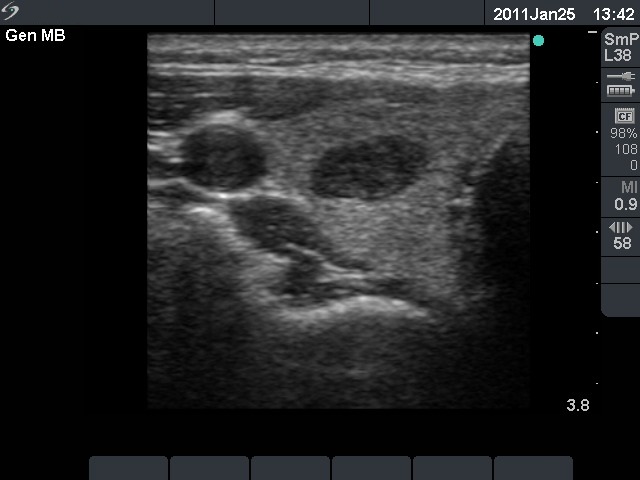

Ultrasonography: a hypoechogenic nodule with a type 3 vascular pattern in the right lobe.